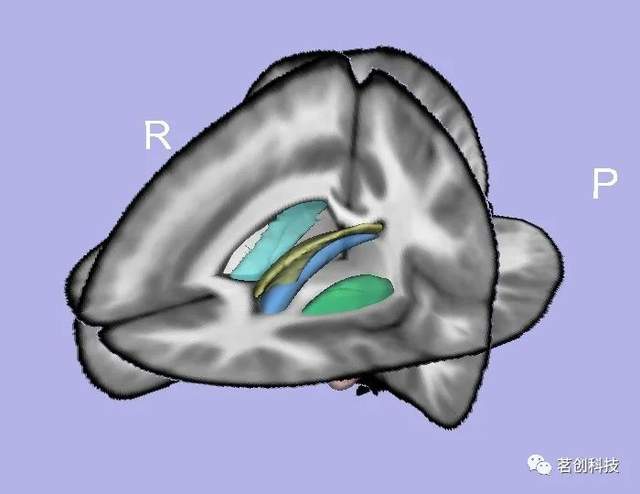

UNC/UCI新生儿海马杏仁核多图谱

这是一组T1和T2加权图像,来自出生后五周内扫描的六个典型发育的新生儿,其中包括灰质、白质和脑脊液,以及海马和杏仁核的分割。

https://www.nitrc.org/projects/unc_brain_atlas/

https://www.med.unc.edu/psych/research/niral/download/download-data